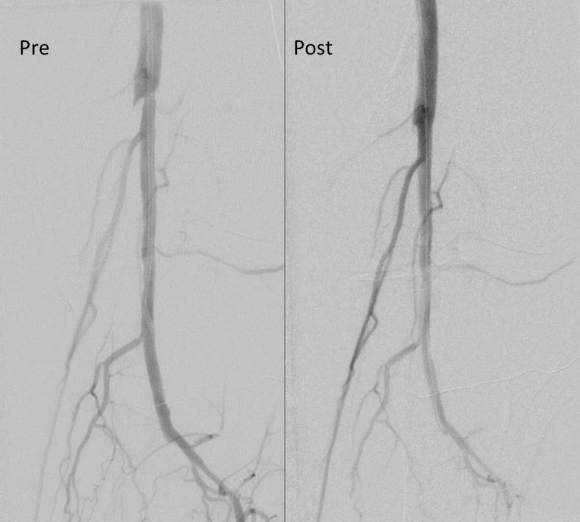

The patient’s right common femoral artery was exposed in the usual manner. Wire access across the occluded external iliac artery was achieved from a puncture of the common femoral artery. Remote endarterectomy (EndoRE) was performed over a wire from the common femoral artery to the external iliac artery origin (pictures below).

The 18F sheath went up with minimal resistance, and the EVAR was performed in the usual manner. The left common iliac artery occlusion was managed percutaneously from a left brachial access. The stent graft on the left was terminated above the iliac bifurcation and a self expanding stent was used to extend across the iliac bifurcation which had a persistent stenosis after recanalization.

The patient recovered well and was sent home several days postprocedure. He returned a month later with healed wounds and palpable peripheral pulses. He no longer had claudication and CTA showed the aneurysm sac to have no endoleak (figures below).